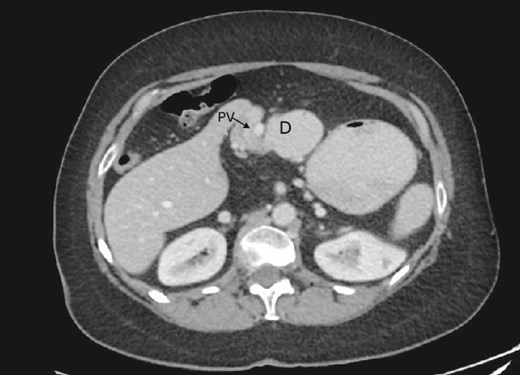

Preduodenal PV seen crossing the duodenum (D) causing partial obstruction.

On examination, the abdomen was soft but mildly distended. Bowel sounds were heard, and the epigastrium was mildly tender. Standard bloodwork was normal. Review of an abdominal computerized tomography (CT) scan from 4 years prior showed congenital malrotation of the bowel, with the small bowel to the left of the midline and colon entirely to the right (Fig. 1). There was partial agenesis of the dorsal pancreas (Fig. 2), azygous continuation of the inferior vena cava (IVC), a retroaortic and retrocrural left renal vein, and an unremarkable spleen alongside some splenules. The PV traversed anterior to the first part of the duodenum (Fig. 3). There was relative narrowing of the distal stomach and the duodenum was nondilated.